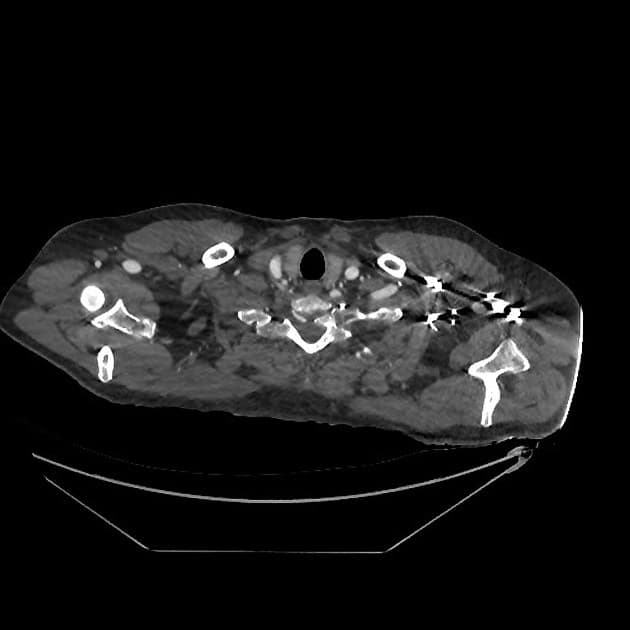

Nhiều ổ khí và hình ảnh tăng đậm đặc/xơ hóa liên quan ở mô mềm vùng trước giữa thân xương đòn trái, phù hợp với chấn thương mô mềm.

Không thấy gãy xương dưới vùng được chụp của xương đòn trái.

- Khí trong mô mềm trước giữa thân xương đòn trái rất gợi ý vết rách mô mềm. Không gãy xương đòn trái, tuy nhiên xương đòn được chụp chưa đầy đủ toàn bộ chiều dài.